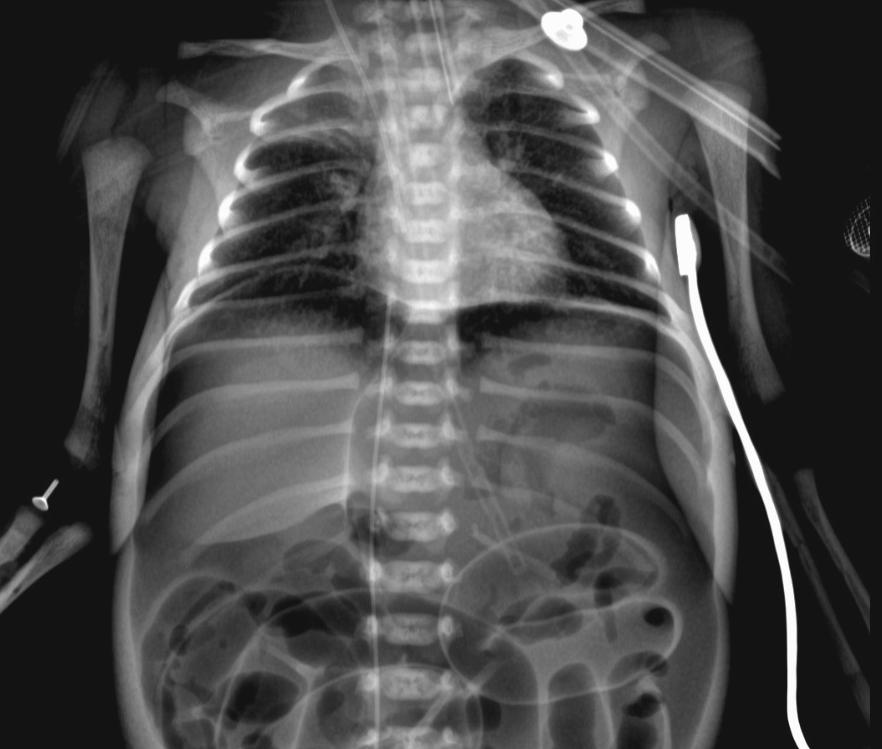

瓜瓜的X光片检查见明显气腹

X光检查显示瓜瓜未见胃腔显影、腹腔中有大量气体,提示消化道穿孔。